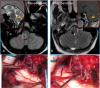

Las malformaciones cavernosas (MC) son anormalidades congénitas de los vasos sanguíneos. Presentamos una paciente con antecedentes en un 1 año, de dos eventos clínicos y radiológicos de sangrado en el tronco cerebral (Bulbo raquídeo),...